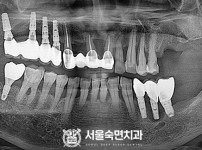

상악동거상술, 뼈이식 / 숙면임플란트 14개 - 네오임플란트 (이*현님)

해당 게시물은 의료법 제56조에 의거하여 로그인 후 열람이 가능합니다.

구분 임플란트